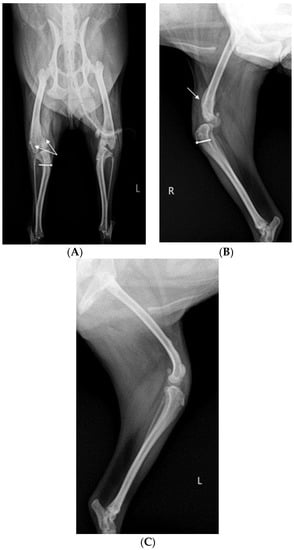

X-ray (E7239X, TOSHIBA, Tokyo, Japan) analysis was conducted. According to radiograph imaging (Weview pacs system, Seoul, Republic of Korea), the screw fixing the bone fragment to the tibial tubercle in the right hind limb had remained, and the patella was not recognized in the radiography view, which was consistent with the results following palpation (Figure 1A,B). Bone proliferation was noted, and edema was observed around the stifle joint (Figure 1A,B). Severe MPL, periostitis, and edema around the stifle joint in the left hind limb were observed (Figure 1A,C). Following a physical examination, complete blood count (Procyte Dx analyzer, Maine, USA) and biochemistry device (Catalyst One chemistry analyzer, Maine, USA) were measured. Neutrophil levels were observed to be slightly increased, namely, 11.71 μL (78.2%), suggesting that inflammatory responses were in progress (Table 1).

Figure 1.

A 2-year-old Pomeranian dog with chronic weight-bearing lameness of the stifle joints in both hind limbs. (A) Craniocaudal radiographic views of the stifle joints of the dog. (B) Lateral radiographic views of the right stifle joints. (C) Medial radiographic views of the left stifle joints. a: osteophyte, b: periostitis, c: residual screw for tibial tuberosity transposition, d: periostitis, R: right, and L: left.

Before surgery, antibiotic and anti-inflammatory drugs were applied for about a month to relieve pain, edema, and arthritis; then, the surgery was performed. For treatment, amoxicillin/clavulanic acid (12.5 mg/kg, Amocla, KUHNIL corp., Seoul, Republic of Korea), carprofen (2.2 mg/kg, RIMADYL, Zoetis Inc., Parsippany-Troy Hills, NJ, USA), tramadol (2 mg/kg, Tridol cap. Yuhan Corp, Seoul, Republic of Korea), and famotidine (0.5 mg/kg, Famotidine, Hanmi Pharm, Seoul, Republic of Korea) were prescribed BID for 4 weeks. After one month, radiographic findings confirmed that inflammation and edema in both stifle joints were reduced (Figure 2). The owner was informed that stifle joint arthrodesis was to be performed on the right hind limb due to severe osteoarthritis, loss of the patella, and rupturing of the cranial cruciate ligament and that MPL correction was to be performed on the left leg. Accordingly, the consent of the guardian was obtained.

Figure 2.

Preoperative craniocaudal (A) and mediolateral (B,C) radiographs of the right and left stifle joints. The prescribed anti-inflammatory drugs reduced pain, lowered fever, and decreased inflammation (swelling and damage) after about a month. Arrows in images show areas with significantly reduced inflammation and edema compared to a month prior.